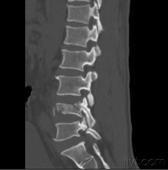

按照Denis三柱概念,爆裂骨折已成為脊柱骨折中具有重要臨床意義的一型,如處理不當(dāng),易引起意外。

Denis等人強調(diào),當(dāng)椎體的后壁和后部纖維環(huán)等結(jié)構(gòu),即包括后縱韌帶的中柱一旦遭受破壞,則可造成前屈狀態(tài)下的不穩(wěn)定,并把此種累及前柱和中柱的骨折定義為爆裂骨折。